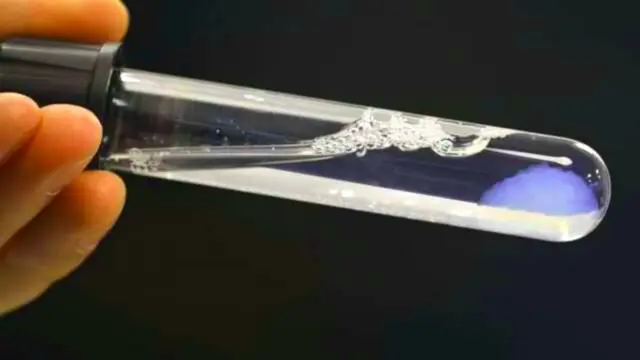

Sus responsables han explicado que todo el procedimiento comienza con el diseño de un páncreas en 3D en una pantalla de ordenador, lo que genera posteriormente una réplica digital del páncreas correspondiente. Al sistema solo le toma 30 segundos para imprimir el tejido en una bioimpresora, con vasos sanguíneos incluidos, y todo a partir de una pequeña muestra de células madre del paciente.

Desde ahí mismo se emplea un gel biológico con las células madre del paciente en su interior, y los ingenieros usan un láser para solidificar el gel a través de la polimerización, controlando al mismo tiempo la intensidad y la dirección del haz para solidificar selectivamente las porciones del gel necesarios para dar forma al tejido en concreto.